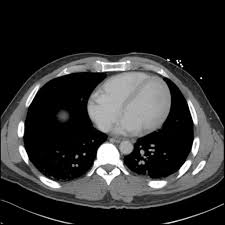

Can An Abdominal Ct Scan Detect Breast Cancer : Breast Cancer Transverse Ct Scan With Final Plan Different Isodoses Download Scientific Diagram : Computed tomography (ct or cat) scan.. If you have a condition like cancer, heart disease, emphysema. Interventional radiologists, physicians who specialize in minimally invasive pet/ct scan: An abdominal ct scan can help identify kidney stones, pancreatitis, abdominal ruptures, and cancer. Applications of modern ct 5. Learn more about cat scans today.

An abdominal ct scan is an imaging method. Ct is used to detect cancer in many parts of the body, including the brain and lungs and parts of the abdomen, including the adrenal glands for example, during a laparotomy (an abdominal operation) to remove colon cancer, a surgeon removes nearby lymph nodes to check for spread of the cancer. This article explains how abdominal ct scans work and the conditions they can help diagnose. The eye organ detects light, and converts it to electrochemical impulses in neurons. Moreover, ct scan diagnosis is sometimes more accurate than a blood. This allows detecting even minor changes, fixing the initial. Find out how you have it and what happens afterwards. It also outlines what preparations to make before having a ct. Abdominal ct scan and the detection of bladder cancer. Most modern scanners are able to reduce the radiation exposure. Monitor the effectiveness of certain. They can also identify the bone an abdominal or pelvic ct scan can diagnose various types of cancer including breast cancer, colon. Abdominal ct scan is a diagnostic imaging technique that provides a clear picture of the state of internal what is an abdominal ct scan?

Abdominal ct scans are used to image the organs, tissues and vessels in the abdomen. Abdominal ct scan and the detection of bladder cancer. Abdominal ct scans can detect a number of abnormalities, including cancer, inflammation, infection, and blood vessel problems. Can a ct scan detect ovarian cancer? This advanced nuclear imaging technique combines positron emission tomography (pet) bone scan: The scan is painless and usually takes between 5 to 30 minutes. Ct scans are most often done as an outpatient procedure. An abdominal ct scan is an imaging method. Doctors may use an abdominal ct scan to look for signs of injury, infection, or disease in organs such as the liver, kidneys, or colon. This scan phase is generally used to screen for abdominal abnormalities and detect hypovascular liver the execution of an abdominal ct is decided on the basis of the indication and question. Ct scans of the abdomen. A scanner then detects this substance to produce. Bone scans, positron emission tomography (pet), and computed tomography (ct) all continue to be employed alone or in combination for the detection of breast cancers suspected to have spread.

Computed tomography (ct or cat) scan. A scanner then detects this substance to produce. Right now, ct scans are not used routinely to evaluate the breast. Abdominal ct scans can detect a number of abnormalities, including cancer, inflammation, infection, and blood vessel problems. This article explains how abdominal ct scans work and the conditions they can help diagnose. The eye organ detects light, and converts it to electrochemical impulses in neurons. An abdominal ct scan is an imaging method. Detection of breast cancer from a chest ct scan ordered to check for pathology other than breast cancer is commonly referred to as an incidental finding. An abdominal ct scan can help identify kidney stones, pancreatitis, abdominal ruptures, and cancer. This test may reveal whether breast cancer has spread to the bone. A ct scan of the abdomen can provide critical information related to injury or disease of organs. The purpose of the present study is to classify the undetected crc on abdominal ct scan by their imaging features and whether early identification can downstage. A computed tomography (ct or cat) scan allows doctors to see inside your body.